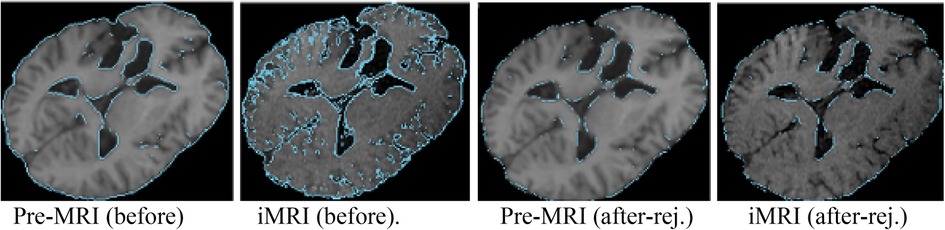

NEMNRR addressed a fundamental challenge in PBNRR: “pre-operative landmarks near the tumor fail to correspond to iMRI landmarks”. The crux of the idea is to use the NEM method to resolve the deformation field with missing correspondence, specifically in the resection region. This has many implications; one is to compute the registration error more accurately than Hausdorff Distance (HD) when correspondence is unknown. Like the PBNRR, the NEMNRR uses the strain energy of the biomechanical model to regularize the solution. Figure 5 shows the results of point outlier rejection produced by NEMNRR; compared to the edges before outlier rejection, most point outliers are removed from pre-MRI and iMRI after outlier rejection.

Figure 5. Point outlier rejection. Two left-most pre-op and iMRI depict (in blue) all edges detected before rejecting outliers, while the right-most figures depict the remaining edge points after outlier rejection.